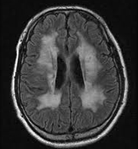

이염성 백질이영양증은 소아의 백질대사 질환 중에서 대표적인 질환입니다. 아릴설파타아제 A(arylsulfatase A)가 감소하여 유발되는 상염색체 열성 유전 질환입니다. 매우 희귀한 병입니다.

아릴설파타아제 A(arylsulfatase A)를 만드는 유전자의 돌연변이가 여러 부위에서 발견되었습니다. 그 유전자는 22번 염색체 장완(22q13-13qter)에 있습니다. 아릴설타파아제 A(Arylsulfatase A)의 결핍이나 부족으로 인하여 cerebroside sulfate(sulfatide)가 중추신경계와 말초 신경의 백질과 수초에 축적됩니다. 이것은 톨루이딘 블루(toluidine blue) 염색 검사를 시행하면 적갈색으로 염색되므로, 현미경으로 관찰할 수 있습니다.

백질에는 광범위하게 탈수초(demyelination)가 일어납니다. 백질은 위축 상태이며, 말기에는 심하게 위축됩니다. 발병 연령과 효소 결핍의 종류에 따라 영아 후기형(late infantile), 연소형, 성인형 등으로 구분합니다.